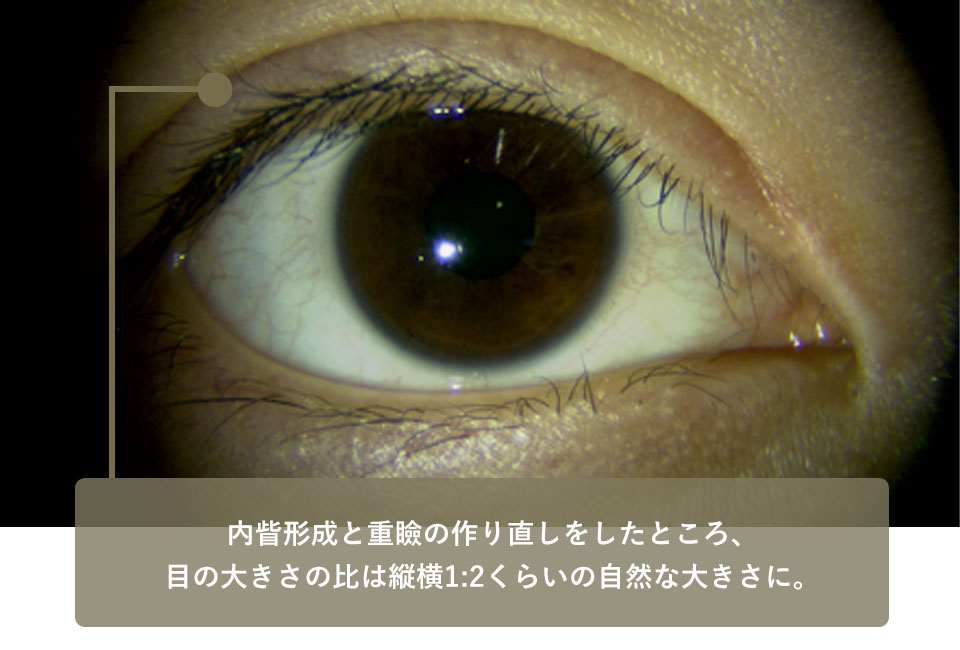

このためこの方には内眥形成術(目頭切開)と上眼瞼の皮膚切除、重瞼作成を行いました。術後、平行型の綺麗な重瞼線が出来て表情も自然になりました。

| 術後 | 皮膚を切除し低い位置で重瞼を作り直し、内眥形成(目頭切開)も行うことで平行型の重瞼が出来た |

|---|---|

| 術後 | 内眥形成と重瞼の作り直しをしたところ、目の大きさの比は縦横1:2くらいの自然な大きさになった |